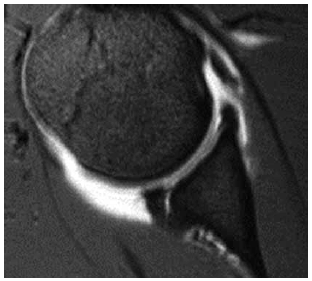

Analise a imagem a seguir e assinale a alternativa que apresenta a lesão observada e o mecanismo mais provável.